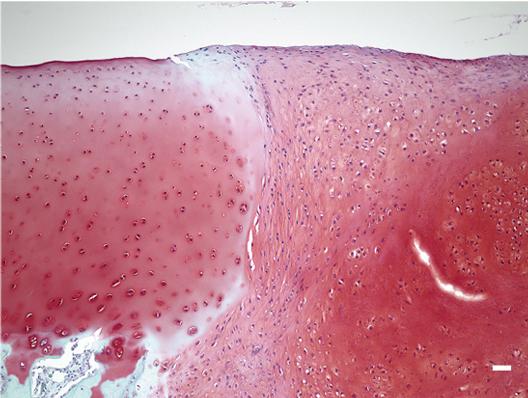

Another advantage to this method is that it avoids the use of artificial scaffolds. In other studies on ES cell- and iPSC-derived chondrocyte transplantation, artificial scaffolds are included into the transplant to provide support until the chondrocytes begin secreting their own ECM proteins. However, it is unclear if artificial materials prevent optimal integration into the cartilage. Because the chondrocytes have already begun secreting ECM proteins, they can be transplanted without scaffolds. This feature is attributed to the use of a suspension culture and medium that included BMP2, TGFβ1 and GDF5 for six weeks. After this time, chondrocytes stopped proliferating and began secreting hyaline cartilage ECM proteins with high purity. This mix of chondrocytes and ECM matrix proteins was harvested as particles 1-2 mm in diameter that could be directly transplanted into the injured tissue (Image 1&2). Each particle contained approximately 70,000 chondrocytes, which according to Tsumaki is good reason to believe enough cells for human transplantation is feasible. "One million chondrocytes are needed to treat 1 cm2 defects, and the area of a typical defect is 2-10 cm2. So, we are considering transplanting 30-150 particles. These numbers are quite manageable."

The team transplanted their particles into three animal models: mouse, rat and mini-pig, finding positive signs for integration and maintenance (Image 3). These results have only encouraged Tsumaki. "These findings are only preliminary, but they show good indications of safety. The next step is to find the best conditions for transplantation in larger animals before we can consider patient treatment."